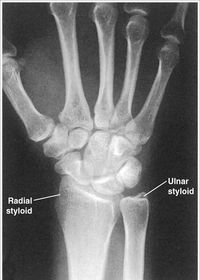

| PA Wrist | ANATOMY: all carpals including midmetacarpals and distal radius/ulna CRITERIA: true PA is marked by symmetry of proximal metacarpals carpals should be free of superimposition of the metacarpals and radius/ulna POSITIONING: CR perpendicular @ midcarpals |

| Oblique Wrist | ANATOMY: carpals on lateral side of wrist, scaphoid CRITERIA: scaphoid well demonstrated 45 degree obliquity POSITIONING: CR perpendicular @ midcarpals |

| L | CRITERIA: radius/ulna should be superimposed thumb should be forward metacarpals superimposed POSITIONING: CR perpendicular @ midcarpals |